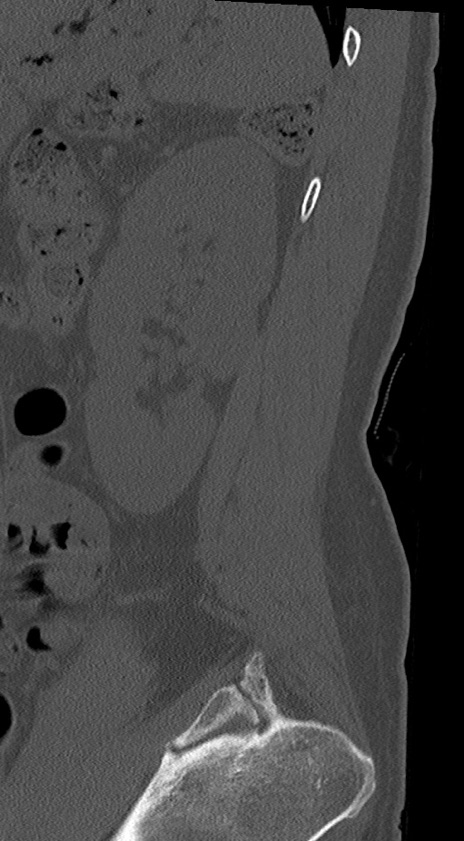

【整形】TIPS症例4 腰椎CT(矢状断像)

腰椎CT